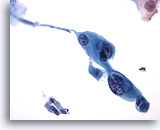

Figure 86

Bronchial wash

Tadpole shaped cells maybe seen in squamous cell carcinoma.

20x

Bronchial wash

Tadpole shaped cells maybe seen in squamous cell carcinoma.

20x